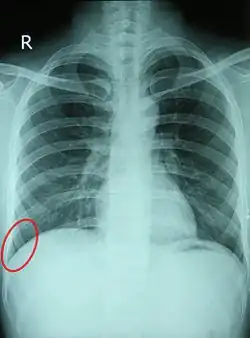

![]() Chest X-ray of a 30-year-old healthy man, with the costodiaphragmatic recess label in red ellipse | |

The costodiaphragmatic recess, also called the costophrenic recess or phrenicocostal sinus,[1] is the posterolateral fringe of the pleural space, a potential space around the lung inside the pleural cavity. It is located at the acutely angled junction ("reflection") between the costal and diaphragmatic parietal pleurae, and is interpreted two-dimensionally on plain X-rays as the costophrenic angle. It measures approximately 5 cm (2.0 in) vertically and extends from the eighth to the tenth rib along the mid-axillary line.

In anatomy, the costophrenic angles are the places where the diaphragm (-phrenic) meets the ribs (costo-).

Each costophrenic angle can normally be seen as on chest x-ray as a sharply-pointed, downward indentation (dark) between each hemi-diaphragm (white) and the adjacent chest wall (white). A small portion of each lung normally reaches into the costophrenic angle. The normal angle usually measures thirty degrees.